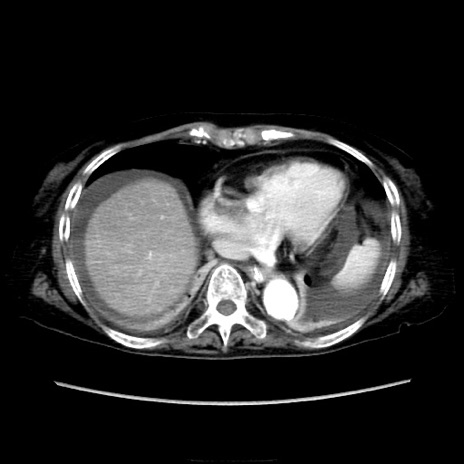

他院CT

横断像